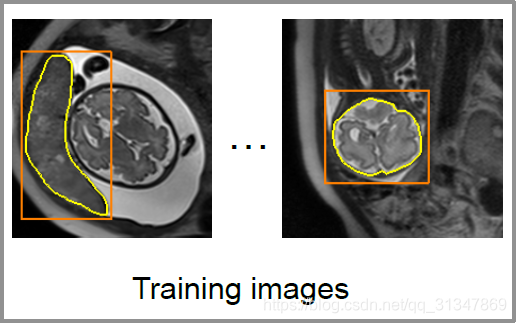

训练过程:

训练图像中包括了实例的分割 label 和检测 bbox(左图),将 bbox 里的内容裁剪下来(中图),前景图像为1,背景为0,然后训练 CNN 网络的参数

θ

0

\theta_0

θ0(右图)。

- T = T = T= { ( X 1 , Y 1 ) , ( X 2 , Y 2 ) , . . . (X_1,Y_1), (X_2,Y_2),... (X1,Y1),(X2,Y2),... },初始训练集,size 为训练集的图片个数(注意与后面 T ^ \hat T T^ 的 size 做区分)

- X p X_p Xp:表示训练集的图片,比如下图的每一张都是一个单独的图像,且每张图像里都可能有多个属于不同类别的实例

- Y p Y_p Yp:训练集图片对应的 label map,也就是 segmentation label(可能有多个 label),对应每张图像里亮黄色的分割线

- l a b e l s e t : T = label\ set:T= label set:T={ 0 , 1 , 2 , . . . , k − 1 0, 1, 2, ... , k-1 0,1,2,...,k−1 }:训练集的类别标签,表示训练集共有 k-1 个类别,每个类对应一个数字标签,背景类标签为 0

将 X p X_p Xp 和 Y p q Y_{pq} Ypq 基于 B p q B_{pq} Bpq 进行裁剪,下图左边是原图 X p X_p Xp 的裁剪结果,右边是二值的 l a b e l m a p Y p q label\ map\ Y_{pq} label map Ypq 的裁剪结果。